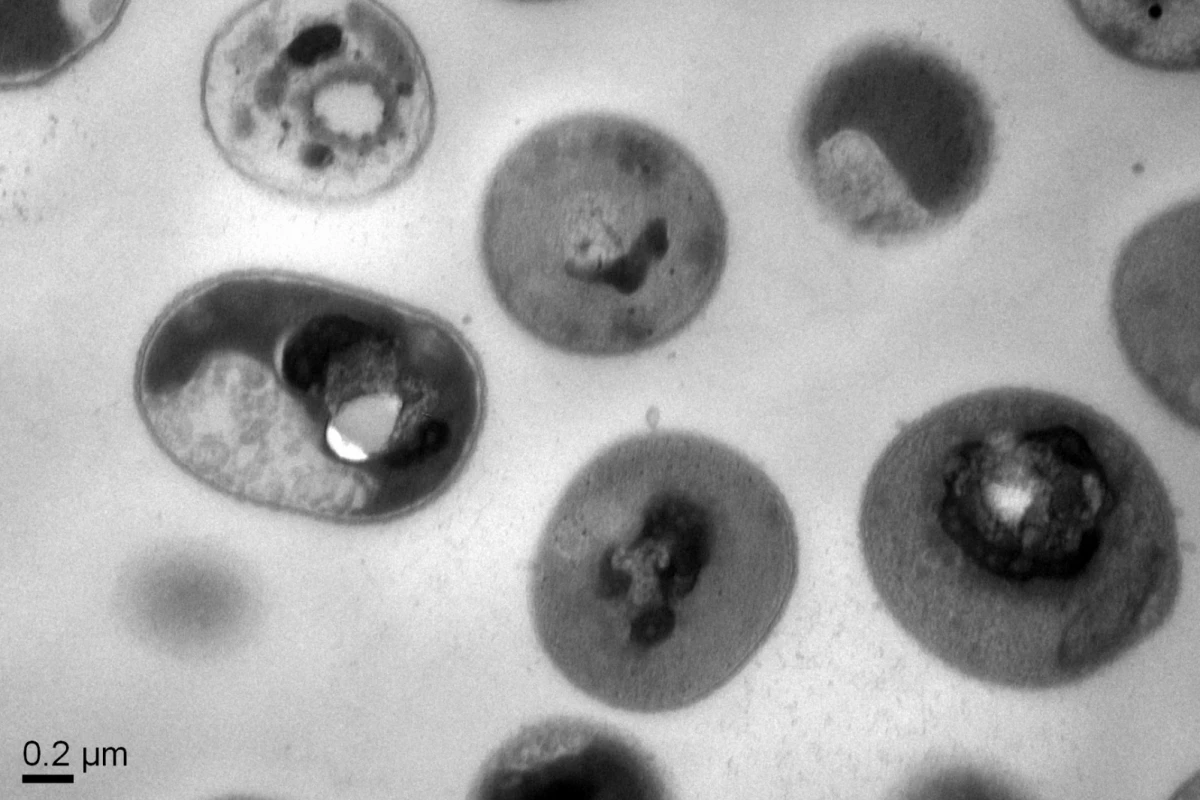

Normal cells of the Acinetobacter baumannii bacteria after treatment with the synthetic polymers, showing that the cytoplasmic substances within the bacterial cell membrane have precipitated, killing the bacteria